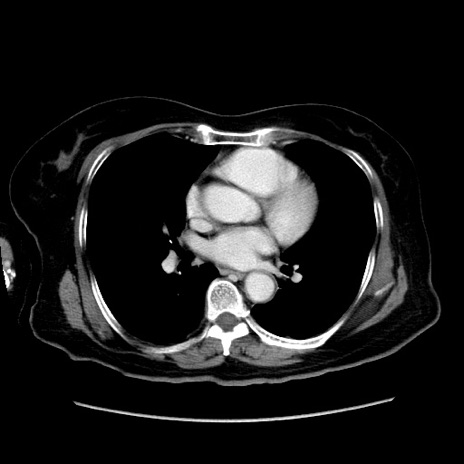

症例19(横断像)

【症例】80歳代女性

【主訴】下腹部痛

【現病歴】約8時間前より下腹部痛の出現あり、救急外来受診。

【既往歴】両側付属器切除

【身体所見】意識清明、下腹部正中に手術痕あり、その部位に一致して圧痛と反跳痛あり。腸蠕動音は亢進。

【データ】WBC 9300、CRP 0.15